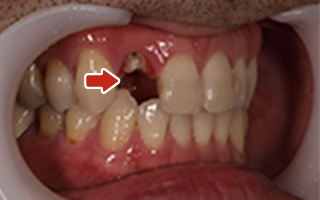

| 45歳 男性 | 医療関係者紹介 |

|---|---|

| 主訴 | 右前歯が取れた(右上2) |

| 処置内容 |

1本インプラント埋入+再生療法 抜歯即時埋入⇒抜歯を行い、同時にインプラント埋入(即時埋入) |

| 治療費用 | 上顎: 約40万円(税込) |

| 治療期間 | 約11ヶ月 |

| リスク | 上部構造物、仮歯の破折、術後の腫れ(3日)、人工歯根脱落リスクがあります |